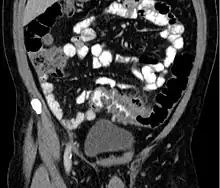

People with the above symptoms are commonly studied with computed tomography, or a CT scan.[41] Ultrasound can provide preliminary investigation for diverticulitis. Amongst the findings that can be seen on ultrasound is a non-compressing outpouching of bowel wall, hypoechoic and thickened wall, or there is obstructive fecalith at the bowel wall. Besides, bowel wall oedema with adjacent hyperechoic mesentery can also be seen on ultrasound. However, CT scan is the mainstay of diagnosing diverticulitis and its complications.[12] The diagnosis of acute diverticulitis is made confidently when the involved segment contains diverticula.[42] CT images reveal localized colon wall thickening, with inflammation extending into the fat surrounding the colon.[43] Amongst the complications that can be seen on CT scan are: abscesses, perforation, pylephlebitis, intestinal obstruction, bleeding, and fistula.[12]